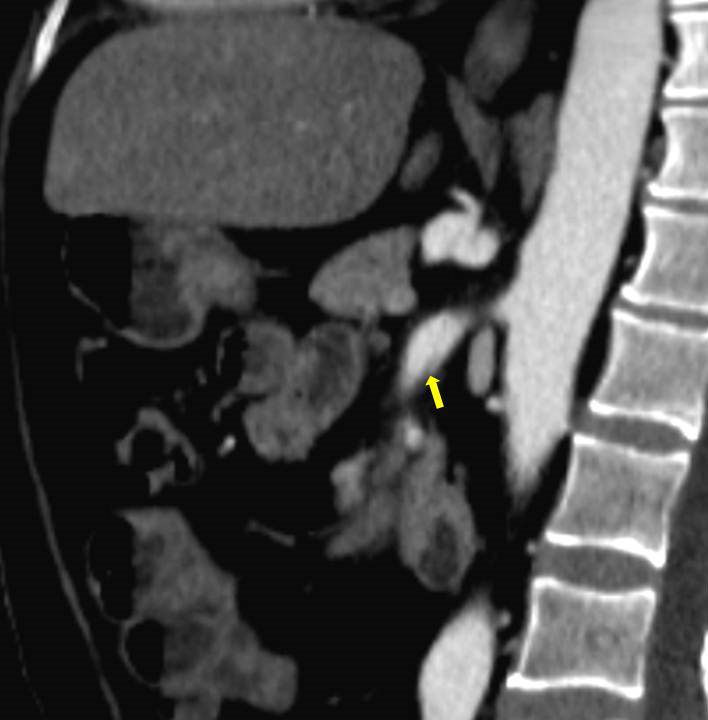

Acute abdominal pain is one of the most common conditions encountered in the emergency department. The differential diagnosis of acute abdominal pain is extensive and identifying the underlying etiology can be challenging. We report a case of acute transient ischemic jejunitis due to symptomatic isolated superior mesenteric artery dissection in a patient with no cardiovascular risk factors or autoimmune diseases. Symptomatic isolated superior mesenteric artery dissection is a rare cause of acute abdominal pain usually treated in the surgical department. The patient had criteria for conservative treatment and rapidly recovered. We highlight a rare condition which should be taken into account for the differential diagnosis of acute abdominal pain.